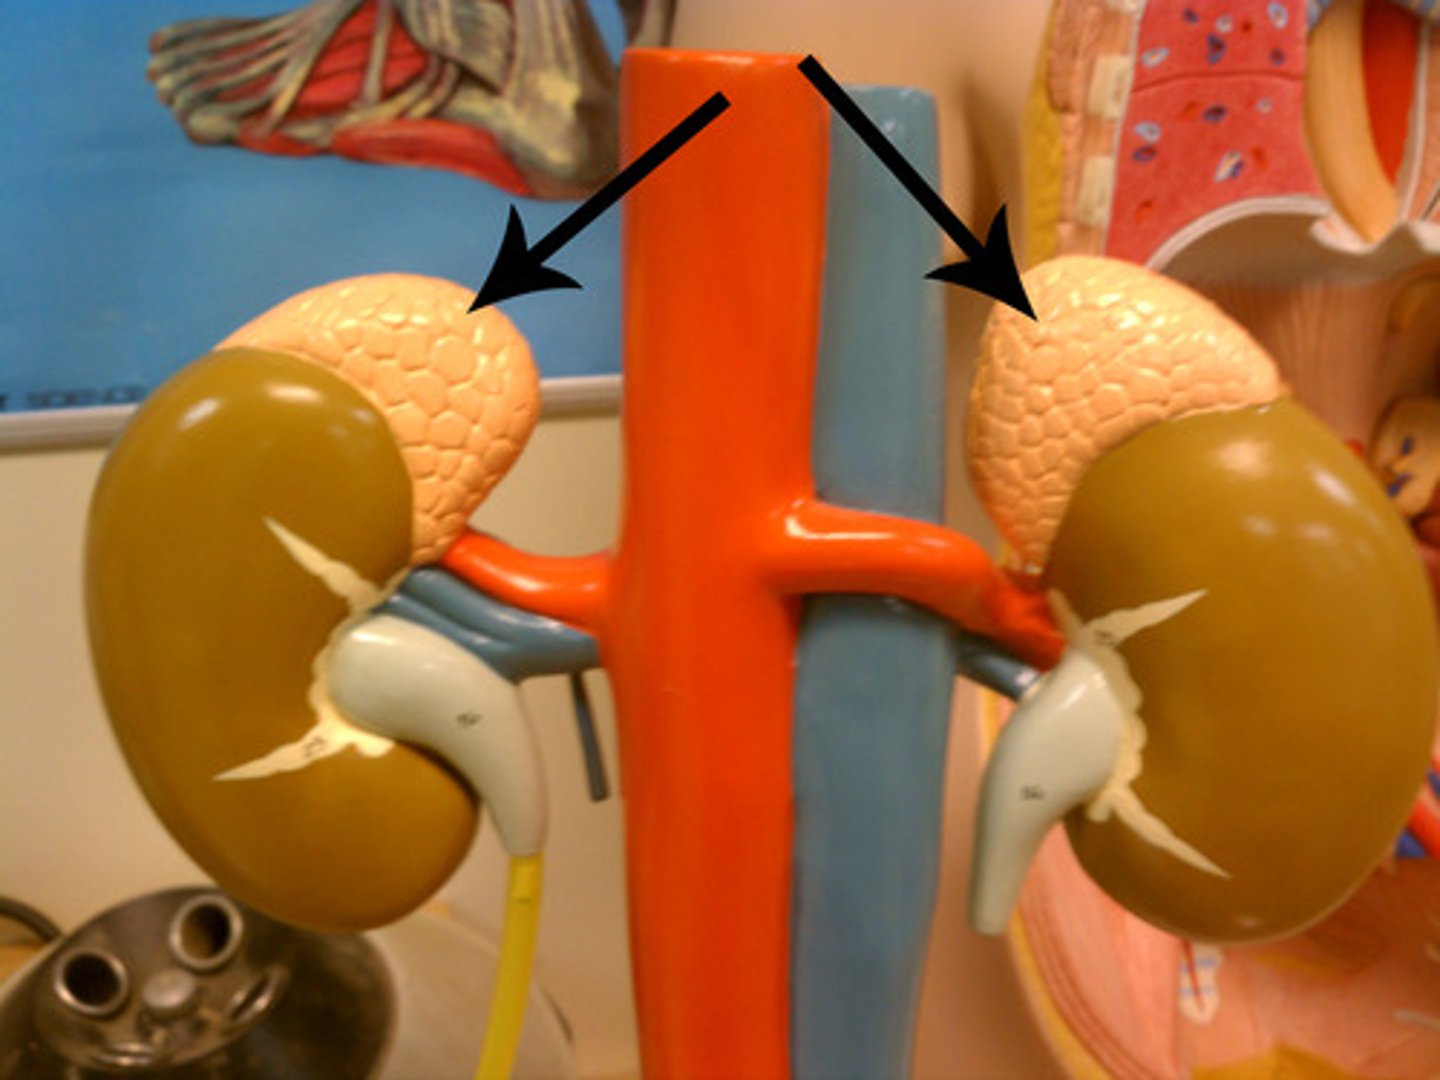

adrenal gland

adrenal gland

arrow

kidney